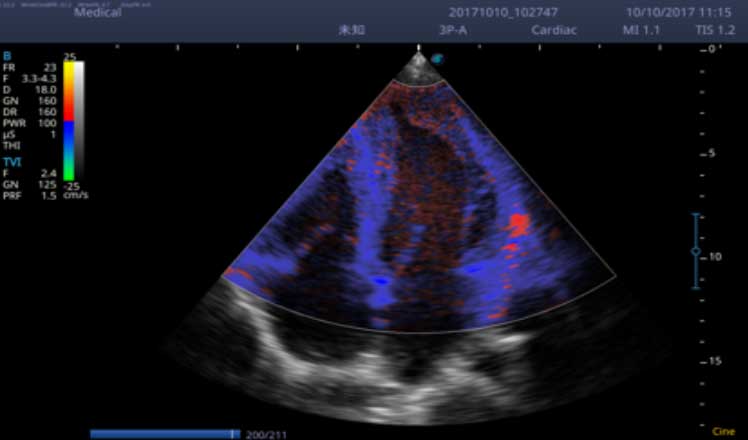

X5采用前端的超声专用芯片,将台式机大规模集成电路完美压缩在笔记本超声的精巧下,提高了系统的运算速度,加载μ-Scan微米成像、脉冲反相谐波等技术,带来优异的临床表现,清晰呈现高分辨率二维图像和层次丰富的血流图像

X5具备实时宽景成像、穿刺增强、彩色M型、组织多普勒等多种高级成像功能,全方位满足多个科室的诊断需求,整机系统向智能化跨越